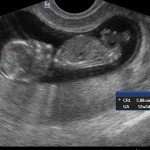

L’ecografia è una tecnica che consente di vedere gli organi del nostro corpo con l’utilizzo di onde sonore ad alta frequenza (ultrasuoni, non udibili dall’orecchio umano) che attraversano i tessuti. La sonda ecografica invia impulsi di onde sonore nel corpo. Quando le onde sonore arrivano al feto mandano degli echi: tali echi (o onde di ritorno) sono trasformati in immagini sul monitor dell’ecografo. Con l’ecografia è quindi possibile osservare in modo dettagliato il feto.

- Perché fare l’ecografia in gravidanza?

Le ragioni più comuni per cui si esegue una ecografia in gravidanza sono: determinare il numero degli embrioni o dei feti, visualizzare l’attività cardiaca fetale, determinare l’epoca di gravidanza, valutare l’anatomia e la crescita fetale, determinare la posizione del feto e della placenta

- Che cosa si vede con l’ecografia?

Nei primi mesi di gravidanza, con la misura della lunghezza del feto, è possibile valutare se lo sviluppo corrisponde all’epoca di gravidanza valutata in base alla data dell’ultima mestruazione, il numero dei feti e la presenza dell’attività cardiaca.

Dal secondo trimestre si misurano altre parti fetali, ed i valori di tali misure vengono confrontati con quelli delle curve di riferimento. Si può così valutare la normalità o meno della crescita fetale. Inoltre periodo si visualizzano la sede di inserzione placentare e la quantità di liquido amniotico.

- E’ possibile rilevare con l’ecografia anomalie fetali maggiori?

La possibilità di rilevare un’anomalia maggiore dipende dalla sua entità, dalla posizione del feto in utero, dalla quantità di liquido amniotico e dallo spessore della parete addominale materna; perciò è possibile che talune anomalie fetali possano non essere rilevate all’esame ecografico. Inoltre alcune malformazioni si manifestano tardivamente (al 7°- 9° mese) e perciò non sono visualizzabili in esami precoci. L’esperienza finora acquisita suggerisce che un esame ecografico routinario, non mirato, consente di identificare dal 30 al 70% delle malformazioni maggiori. Non è compito dell’ecografia la rilevazione delle cosiddette anomalie minori (Linee Guida SIEOG 2006).

- L’ecografia è innocua per il feto?

Gli ultrasuoni sono utilizzati nella pratica ostetrica da oltre 40 anni e non sono stati riportati effetti dannosi, anche a lungo termine, sul feto. Per tale ragione, con le procedure oggi adottate, l’uso diagnostico dell’ecografia è ritenuto esente da rischi. Ovviamente, come in tutte le cose, è bene non eccedere oltre la necessità facendo frequenti esami non necessari.

A fianco alla più tradizionale ecografia eseguita per via transaddominale, risulta particolarmente utile nell’esame ecografico ostetrico e ginecologico la via di accesso transvaginale.

Con questa metodica, utilizzando delle sonde ecografiche appositamente predisposte (per forma e dimensione, e per frequenza di emissione degli ultrasuoni) è possibile controllare la gravidanza nel primo trimestre con una qualità e definizione d’ immagine nettamente superiori a quanto possibile per via transaddominale.

Per eseguire l’ecografia transvaginale non è richiesta la vescica piena, diversamente rispetto a quanto richiesto per l’ecografia transaddominale. L’approccio transvaginale consente di aggirare l’ostacolo dovuto ad un aumentato spessore della parete addominale (obesità). In questi casi infatti la qualità d’ immagine in caso di ecografia transaddominale viene fortemente penalizzata dall’eccessivo spessore del pannicolo adiposo addominale.

Con l’ecografia transvaginale è possibile vedere dopo circa 3 settimane dal concepimento la camera gestazionale nella cavità uterina. Successivamente è possibile visualizzare l’embrione (3-5 mm.) a circa 6 settimane dall’ultima mestruazione (4 settimane dal concepimento) ed a questo periodo è già visibile l’attività cardiaca fetale Anche i primi dettagli sulla morfologia fetale (polo cefalico, abbozzi degli arti) sono visualizzabili più precocemente con l’ecografia transvaginale, risultando essi visibili intorno a 8-9 settimane.

Con l’ecografia dei primi mesi di gravidanza, si può anche valutare la normalità dell’utero (eventuale presenza di fibromi già preesistenti alla gravidanza) e delle ovaie.

Con il finire del primo trimestre per il controllo ecografico di routine della gravidanza la via transvaginale viene poi sostituita dalla via transaddominale.

Successivamente può risultare utile il ricorso all’ ecografia transvaginale nei casi in cui si sospettino delle modificazioni precoci (raccorciamento) del collo dell’utero, come potrebbe verificarsi nei casi di minaccia d’ aborto o di parto pretermine.

In questi casi infatti è possibile con l’ ecografia misurare con precisione la lunghezza del collo uterino. In questi casi inoltre l’ ecografia può anche evidenziare un’ iniziale dilatazione dell’ orifizio uterino interno. Tali modificazioni del collo dell’ utero, valutabili con accuratezza solo con l’ ecografia transvaginale, hanno una grande importanza nel considerare un eventuale rischio di parto pre-termine.